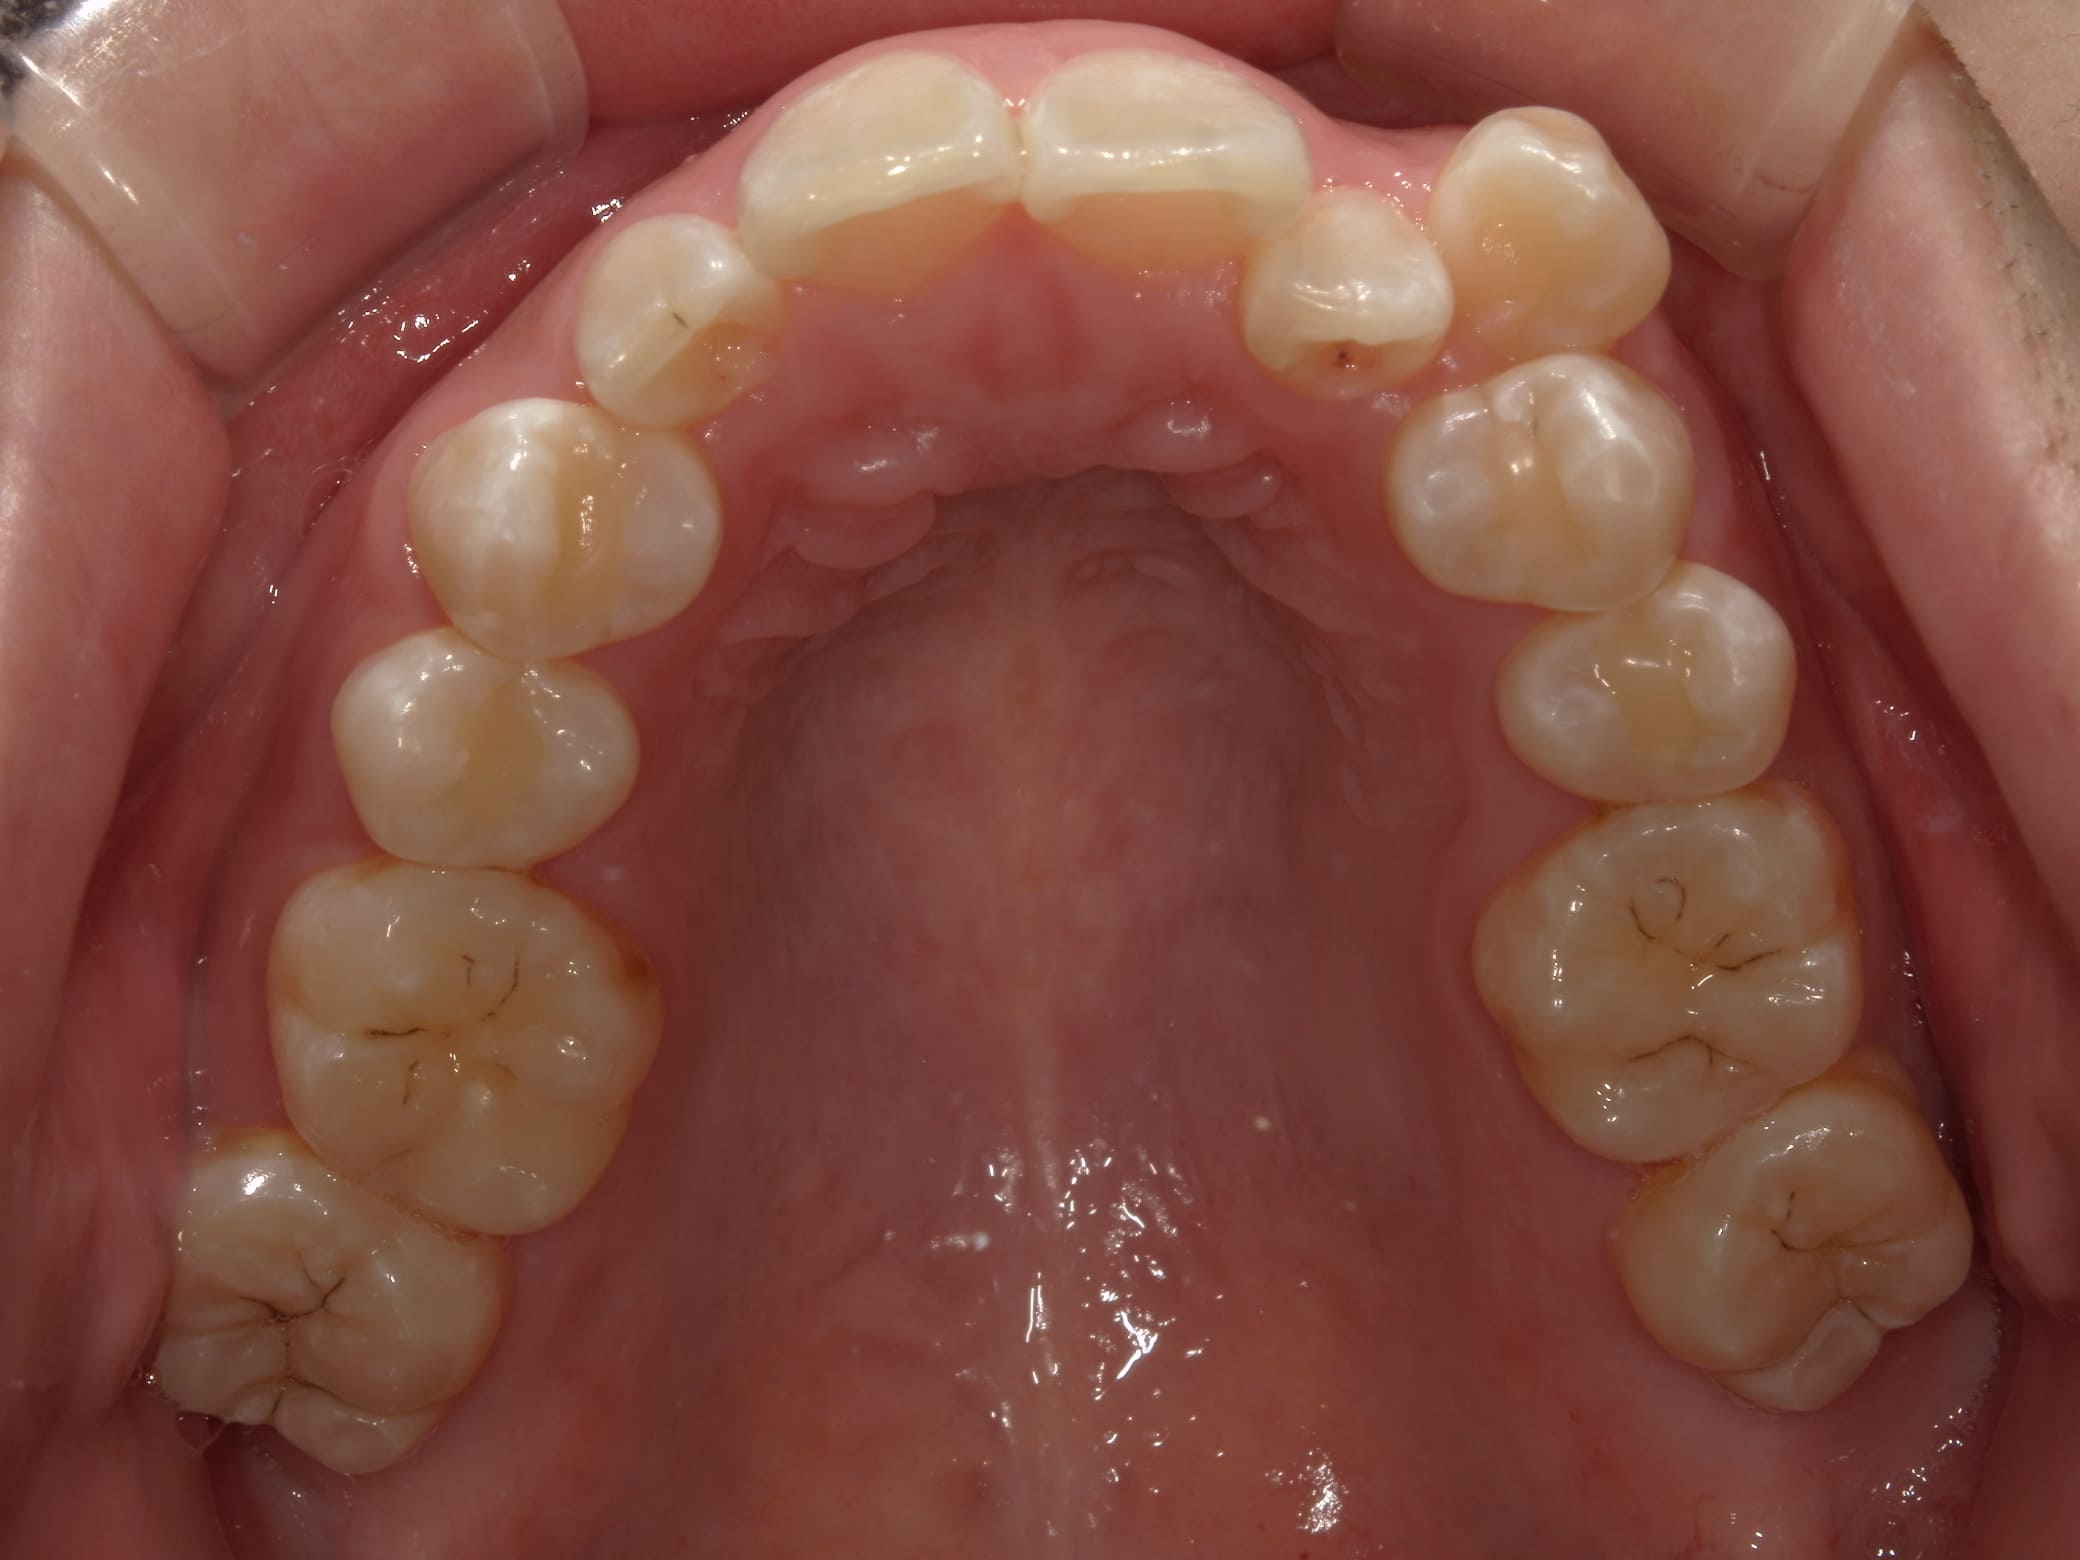

| 主訴 | 叢生が気になる |

| 治療期間・回数 | 1年 |

| 費用 | 935,000円 |